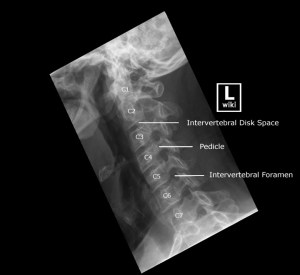

Image source from WikiRadiography (Wetpaint) here.